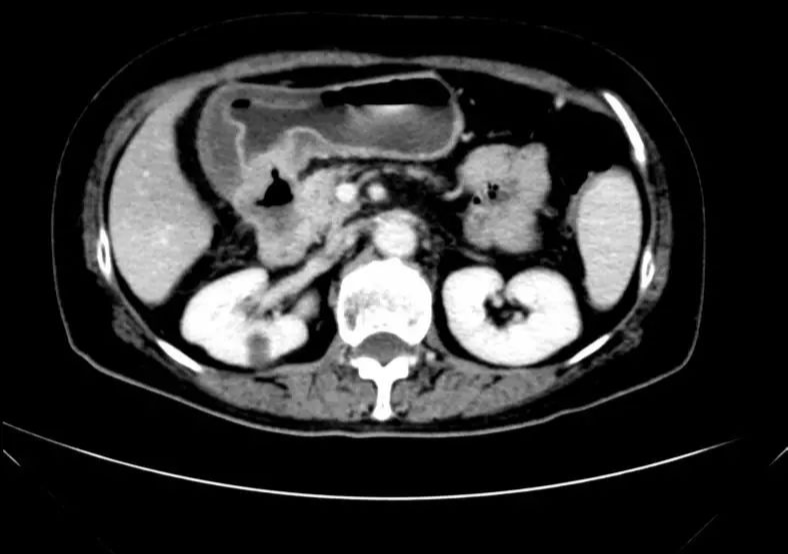

CT-T

CT-H1

MR-H1

影像学检查结果评估:cPD。